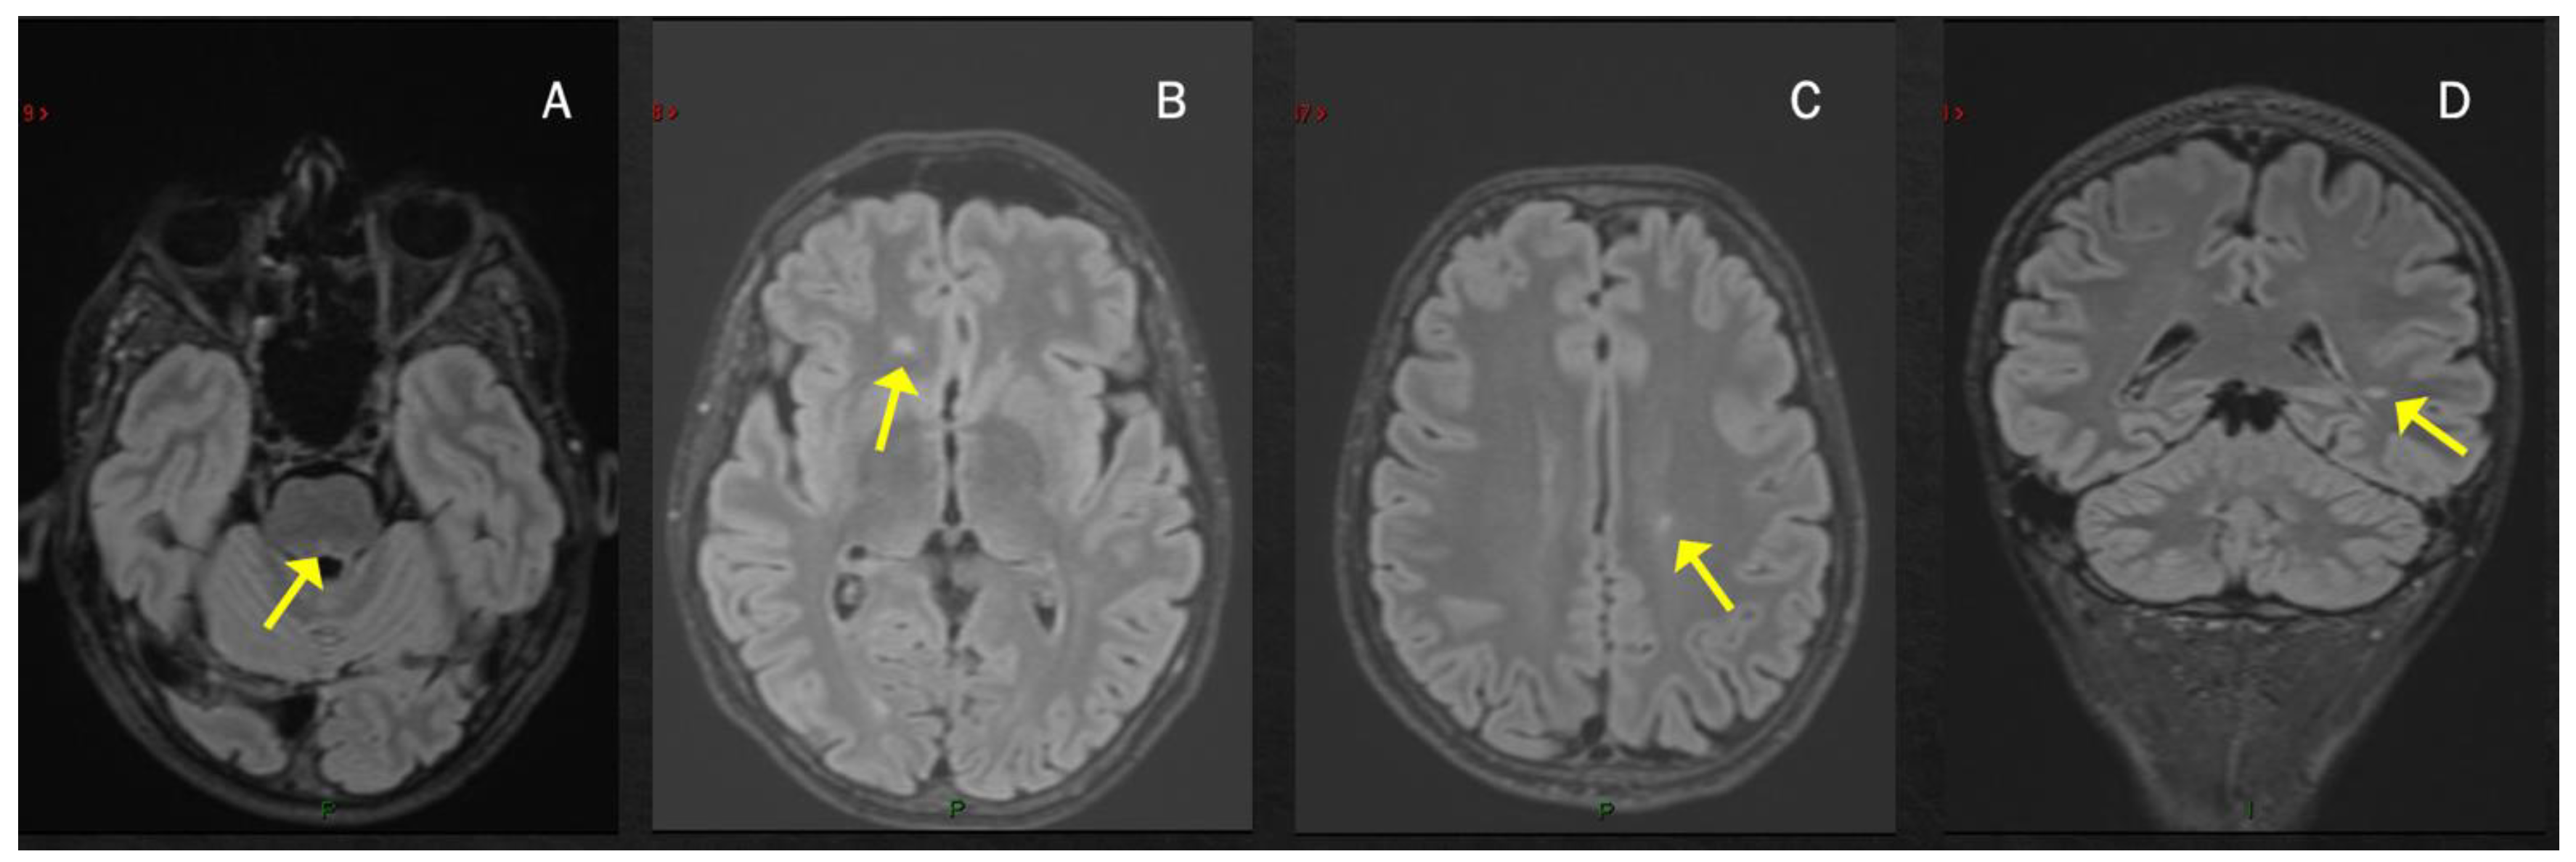

2. MS Onset after SARS-CoV-2 Exposure

| Case 1 | 2 weeks | BS (dyplopia) | - | + | + | - | +/+ |

| Moore et al. [52] | 2 weeks | BS (dyplopia) | BS, ST | + | + | NA | +/+ |

| Yavari et al. [53] | 3 weeks | BS (dyplopia) | ST | + | NA | NA | -/- |

| Carta et al. [54] | concomitant | BS (dyplopia) | ST ^ | + | NA | -/- | |

| Pignolo et al. [55] 1st case | 8 weeks | BS (facial palsy) | - | + | + | - | +/+ |

| Ismail et al. [76]. | 8 weeks | Cerebellum | - | + | + | - | -/- |

| Case 2 | 2 weeks | ON | - SC | + | - | - | +/+ |

| $ Case 3 | 2 weeks | ON | - | + | + | - | +/+ |

| Palao et al. [56] | 2 weeks | ON | ST | + | + | - | +/+ |

| Sarwar et al. [57] | 3 weeks | ON and unilateral motor deficit | ST | + | NA | NA | -/- |

| Case 4 | 4 weeks | SC | SC | + | + | + | +/+ |

| Fragoso et al. [58] | 6 months | SC | ST, SC | + | + | - | +/+ |

| Avila et al. [59] * | 2–6 weeks | 40% SC 40% ON 20% BS | NA | NA | + | 80% - 20% + | NA/+ |

| Feizi et al. [60] | 1 week | SC | SC | + | + | NA | +/+ |